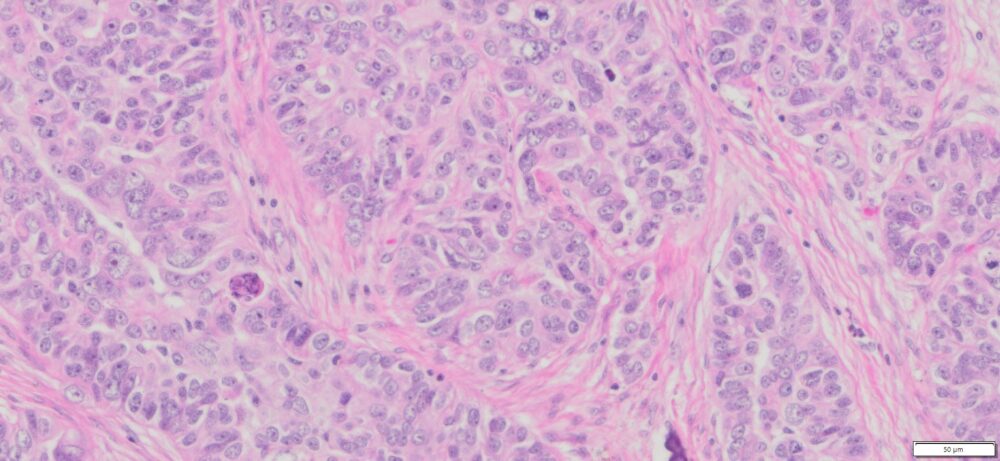

Description

| Organ& Tissue | Pathology Diagnosis | Gender/Age | % Tumor Area | Grade | TMN Stage | IHC Biomarkers |

| Human Ovary | High Grade Serous Carcinoma (HGSC) FFPE Sections | Female/67 | 80% | III | NA | ER(+),Pax-8 (+),WT-1(+),p16(+),p53(+),Ck7 (+), CK20(-) |